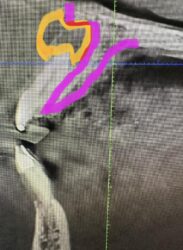

Case I got yesterday. Patient really wants an implant at #18 site. Fun case! ~60yo female, non-smoker, no DM, no osteoporosis or any other bone-related diseases.

How does one clean that PARL adequately, avoid disturbing the IA, and graft reliably. That is a fun case!